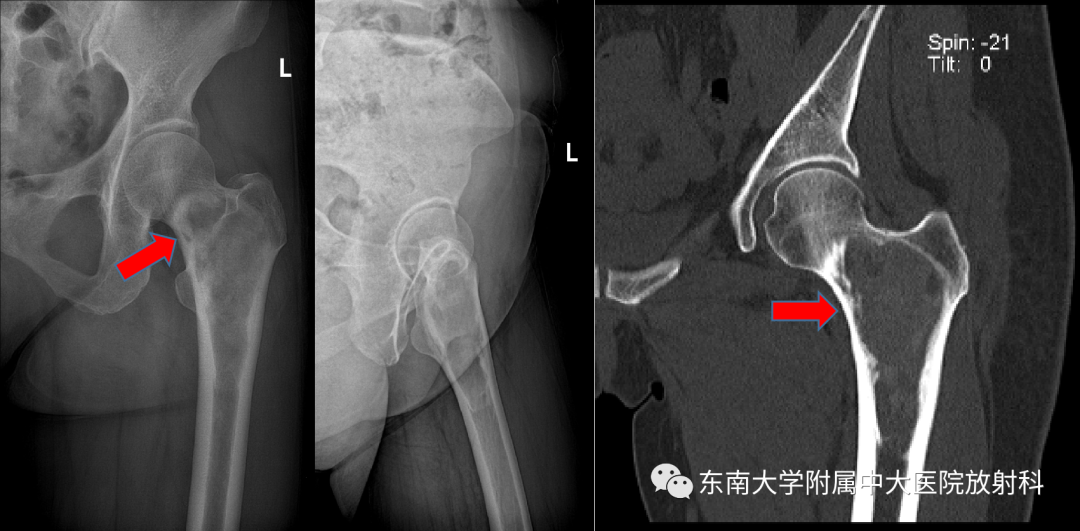

病例

•女,46岁

•主诉:左侧腹股沟区疼痛2月余

•现病史:患者2月余前无明显诱因左侧腹股沟区出现疼痛,呈持续性酸胀痛,休息后缓解,偶有感觉异常